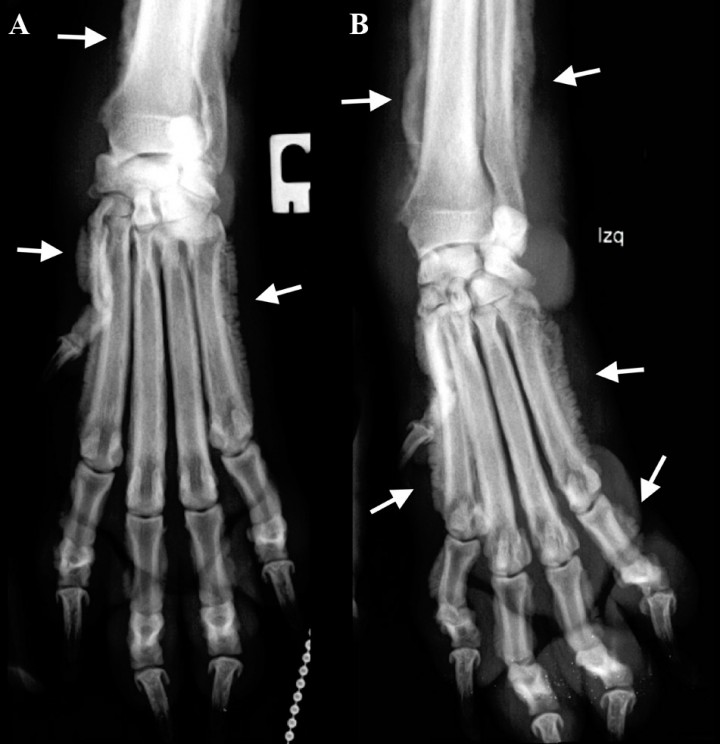

<p>Proyección dorsopalmar de la zona del carpo y metacarpo. <strong>(A)</strong> Derecha.<strong> (B) </strong>Izquierda. </p>

Proyección dorsopalmar de la zona del carpo y metacarpo. (A) Derecha. (B) Izquierda.

<p>Mismas radiografías de la Figura 1. Se observa reacción perióstica del tipo en empalizada (ver flechas) con afectación de la falange media de 2º dedo, en el aspecto lateral y medial de las falanges proximales (dedo I, II, III, IV, V), en el aspecto lateral del cuerpo del hueso metacarpiano I, II y V y del III y IV de forma más leve, y del tercio distal del cúbito y radio. No existe afectación de las superficies articulares ni destrucción ósea. Tumefacción de los tejidos blandos en la zona del carpo.</p>

Mismas radiografías de la Figura 1. Se observa reacción perióstica del tipo en empalizada (ver flechas) con afectación de la falange media de 2º dedo, en el aspecto lateral y medial de las falanges proximales (dedo I, II, III, IV, V), en el aspecto lateral del cuerpo del hueso metacarpiano I, II y V y del III y IV de forma más leve, y del tercio distal del cúbito y radio. No existe afectación de las superficies articulares ni destrucción ósea. Tumefacción de los tejidos blandos en la zona del carpo.